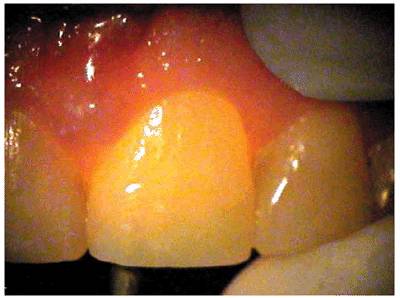

Transillumination via a fiber-optic light may be of great assistance in

detecting color shifts in a crown (Figures 19-1A, and 19-1B). A tooth with a pink or reddish

hue would more than likely indicate internal hemorrhage from a recent injury (Figure 19-2), a dental procedure (Figure 19-3), or gingival tissue hyperplasia

Figure 19-1A: Transillumination of a maxillary left central incisor with a necrotic pulp.

Figure 19-1B: Transillumination of the adjacent tooth with a vital pulp. Because there is active blood flow through the live pulp tissue, the tooth appears brighter to the fiber-optic light than the adjacent tooth with a necrotic pulp.